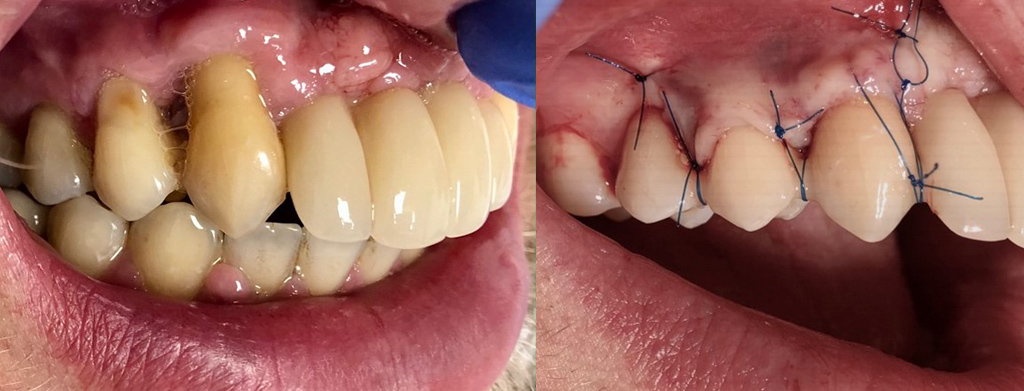

Zabieg gingiwoplastyki i wydłużenia korony klinicznej (przed i po zabiegu)

Chirurgia: dr n.med. Ewa Zawiślak